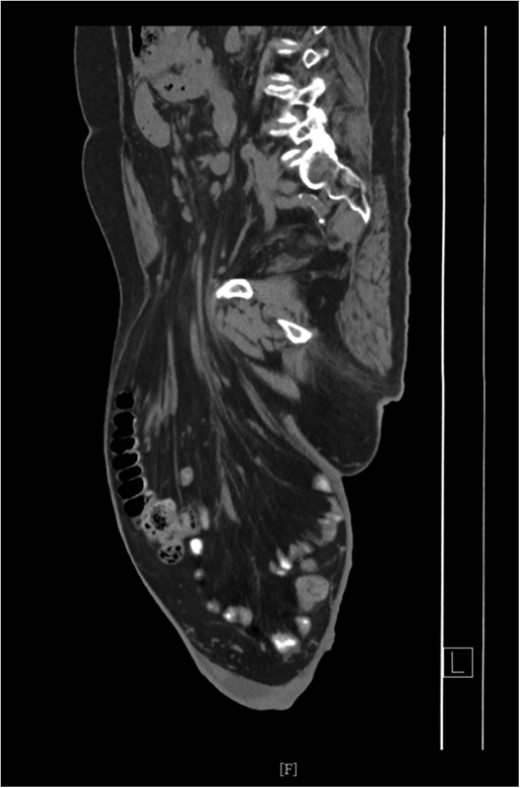

Pulmonary function test revealed no abnormalities. Electrocardiogram was normal, however, an echocardiogram confirmed systolic congestive heart failure with an ejection fraction of 30%. Patient preoperatively underwent a rigorous respiratory exercise and cardiac evaluation. Pre-operative computed tomography (CT) scan showed omentum, small and large bowel within the left scrotum Figs 2 and 3. Consent for the procedure was obtained including orchiectomy, bowel resection. Patient was mechanically bowel prepared the night prior to surgical intervention.

CT Scan showing small and large bowel within left scrotal sac.